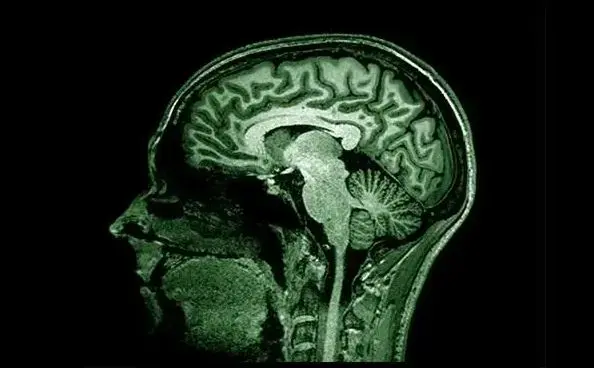

Caracterizada por el deterioro cognitivo y la pérdida de memoria, aparece cuando en las placas cerebrales se produce un exceso de la proteína beta-amiloide. Esta es esencial para la transmisión de información entre neuronas, y la disminución de otra, el tau positivo, empeorando el proceso cognitivo.

Antes incluso de que aparezcan los primeros síntomas, estos depósitos van formando placas entre las neuronas que resultan tóxicas y son los responsables del progresivo deterioro cognitivo.